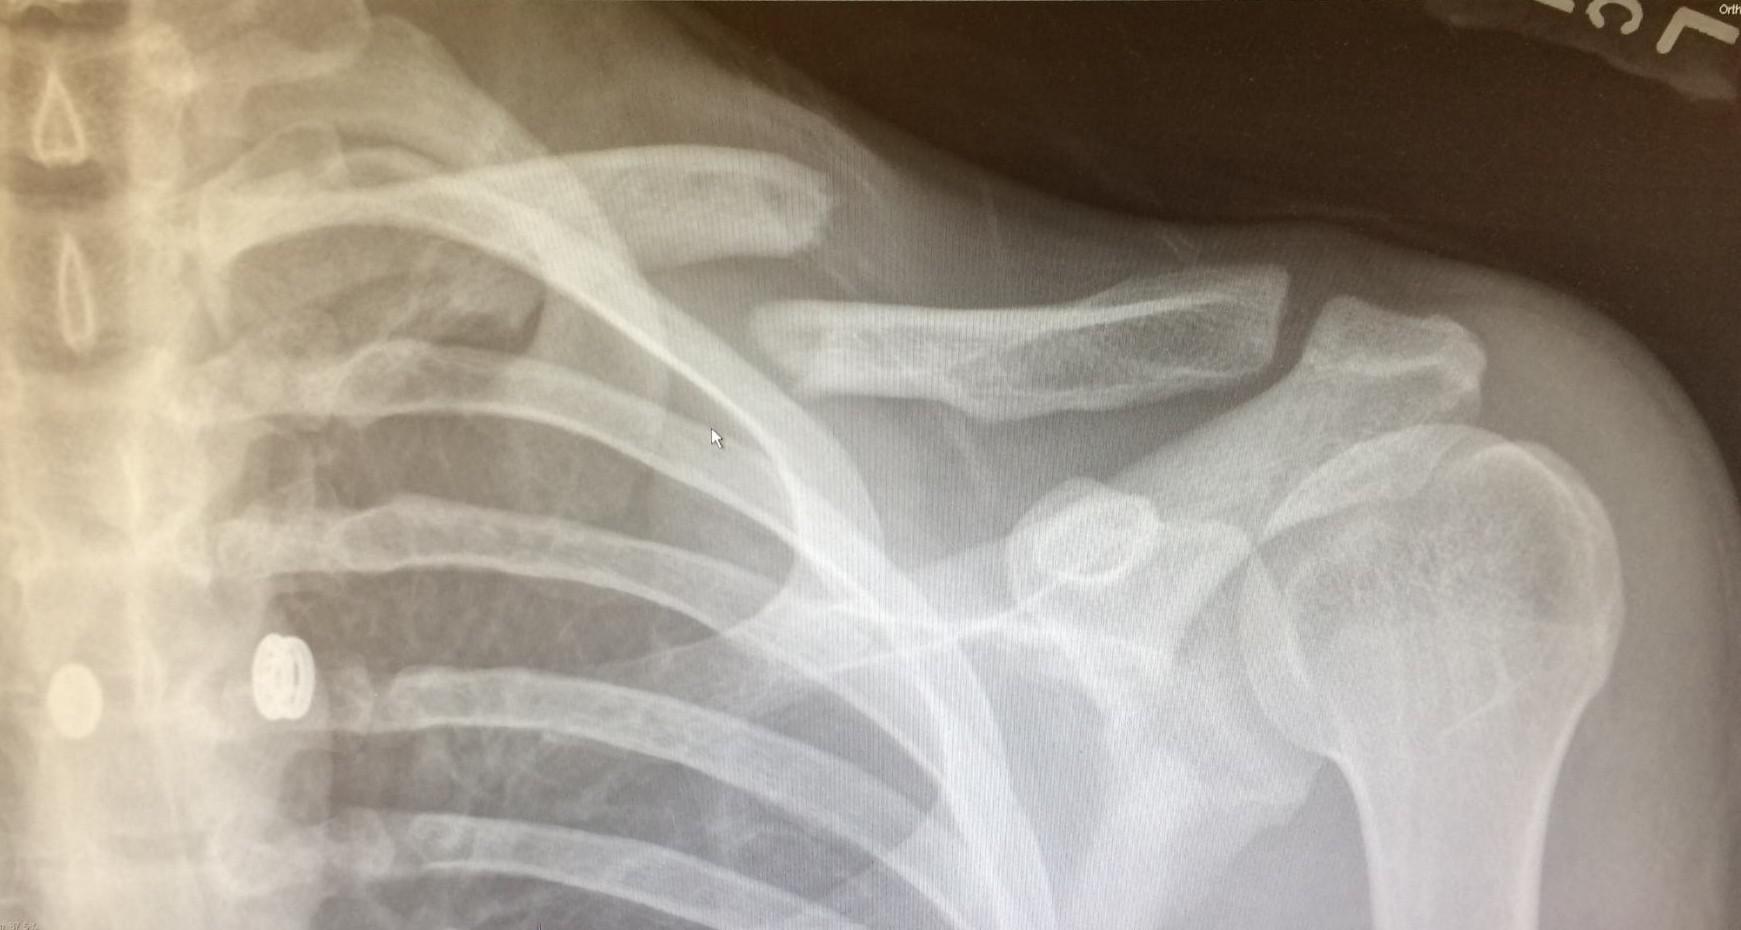

Posterior Displacement of a Proximal Epiphyseal Clavicle Fracture

Posterior Displacement of a Proximal Epiphyseal Clavicle Fracture Pain Under Left Clavicle After Eating The most common symptom of chronic pancreatitis is repeated episodes of severe pain in your tummy (abdomen). The main symptom of pancreatitis is pain felt in the upper left side or middle of the abdomen. If you experience sudden or intermittent pain under your left rib cage or breast, especially after eating or while seated, you will need to understand. Pain Under Left Clavicle After Eating.